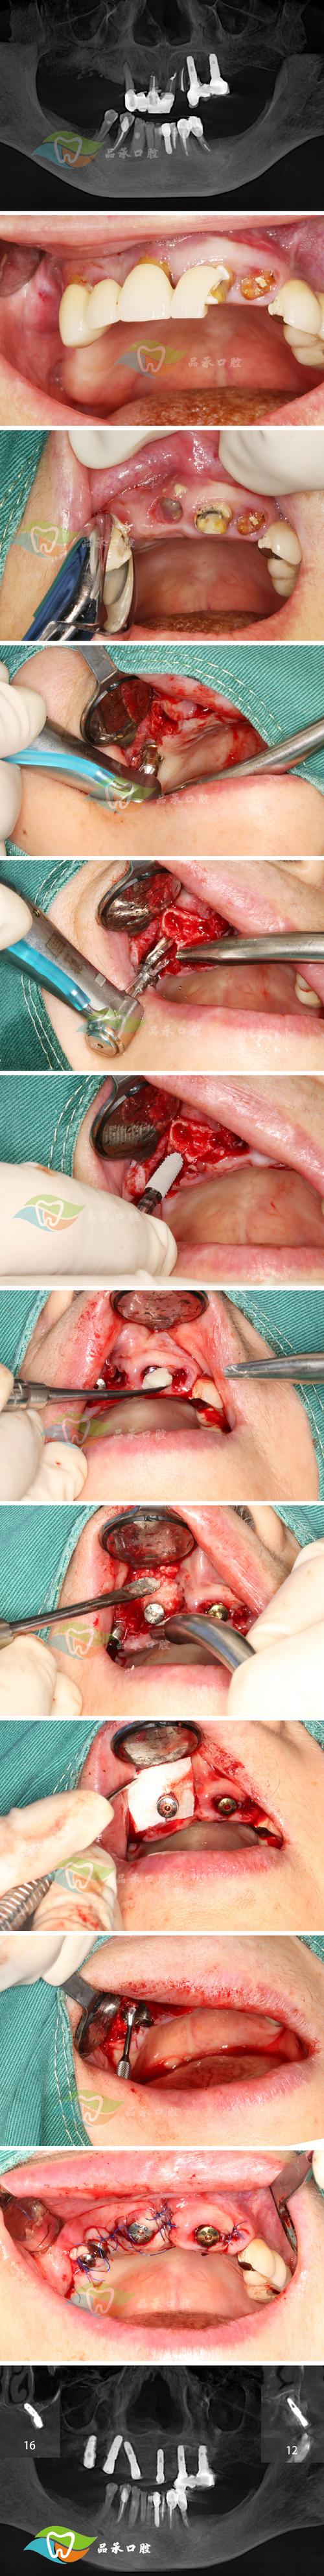

手术过程中,医生需切开牙龈、翻开牙龈瓣(即“翻瓣”),彻底清除牙根表面的牙结石、菌斑及病变的牙骨质,同时可能去除部分病变的牙槽骨,再植入骨粉引导骨再生,这些操作会对牙龈、牙槽骨及牙周韧带等软硬组织造成机械性损伤,术后局部组织会释放炎症介质(如前列腺素、白三烯),刺激神经末梢,引发疼痛。